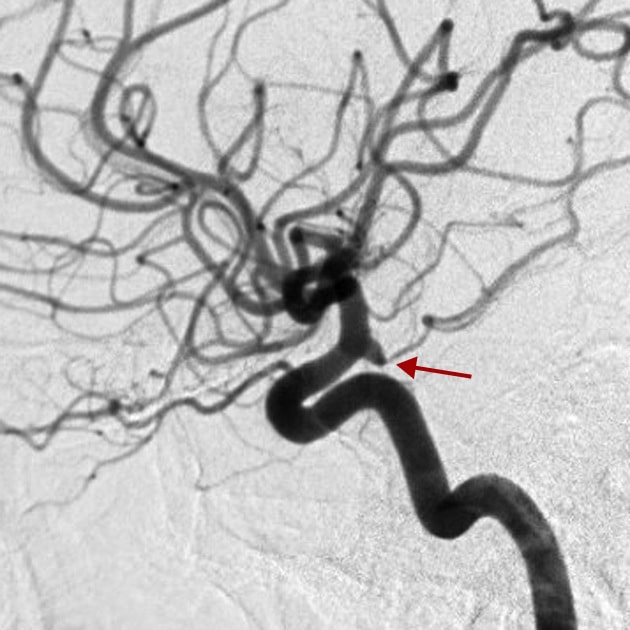

Na imagem abaixo, vemos um pequeno vaso se originando da ectasia infundibular de formato triangular na origem da artéria comunicante posterior.

A dilatação infundibular, ectasia infundibular ou simplesmente infundíbulo é uma dilatação de uma artéria que ocorre na sua origem, ou seja, no ponto em que ela se ramifica a partir de outro vaso maior. Essa dilatação é geralmente pequena (menor que 3 mm), de formato triangular e tem a ver com a formação embrionária do próprio vaso.

Como vimos, as ectasias infunbiulares são pequenas, sempre em formato triangular e na origem dos vasos. Além disso, em geral não causam riscos de sangramento.